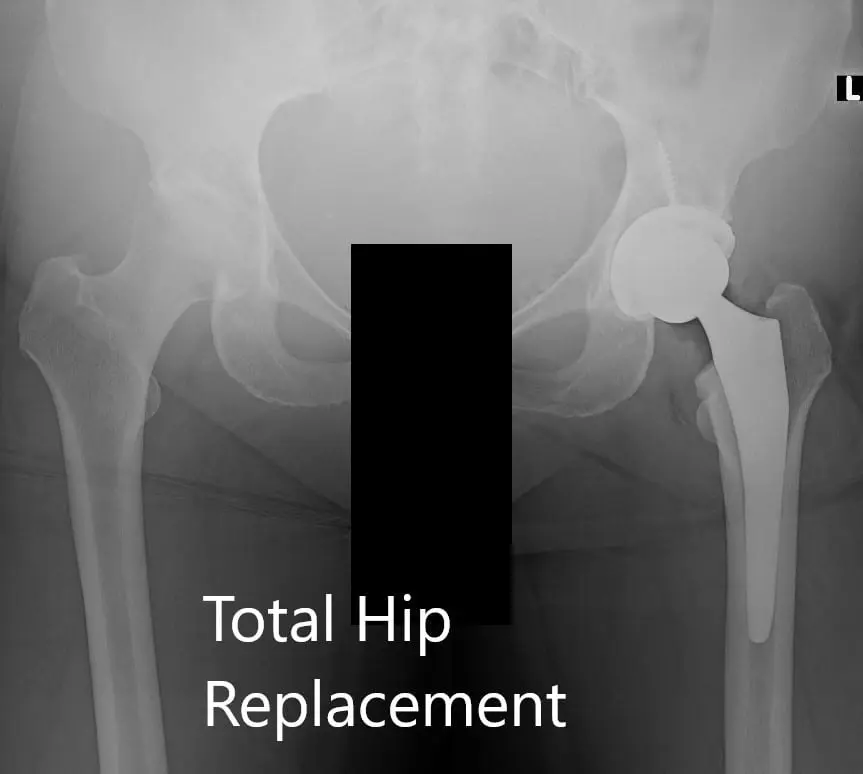

Operation: Left total hip arthroplasty.

Implant used: Acetabular shell 60 mm with a 6.5 mm x 30 mm cancellous screw, with ceramic femoral head 36 mm, 0-degree polyethylene with 127-degree neck angle hip stem.

Postoperative X-ray of the pelvis showing AP and lateral views